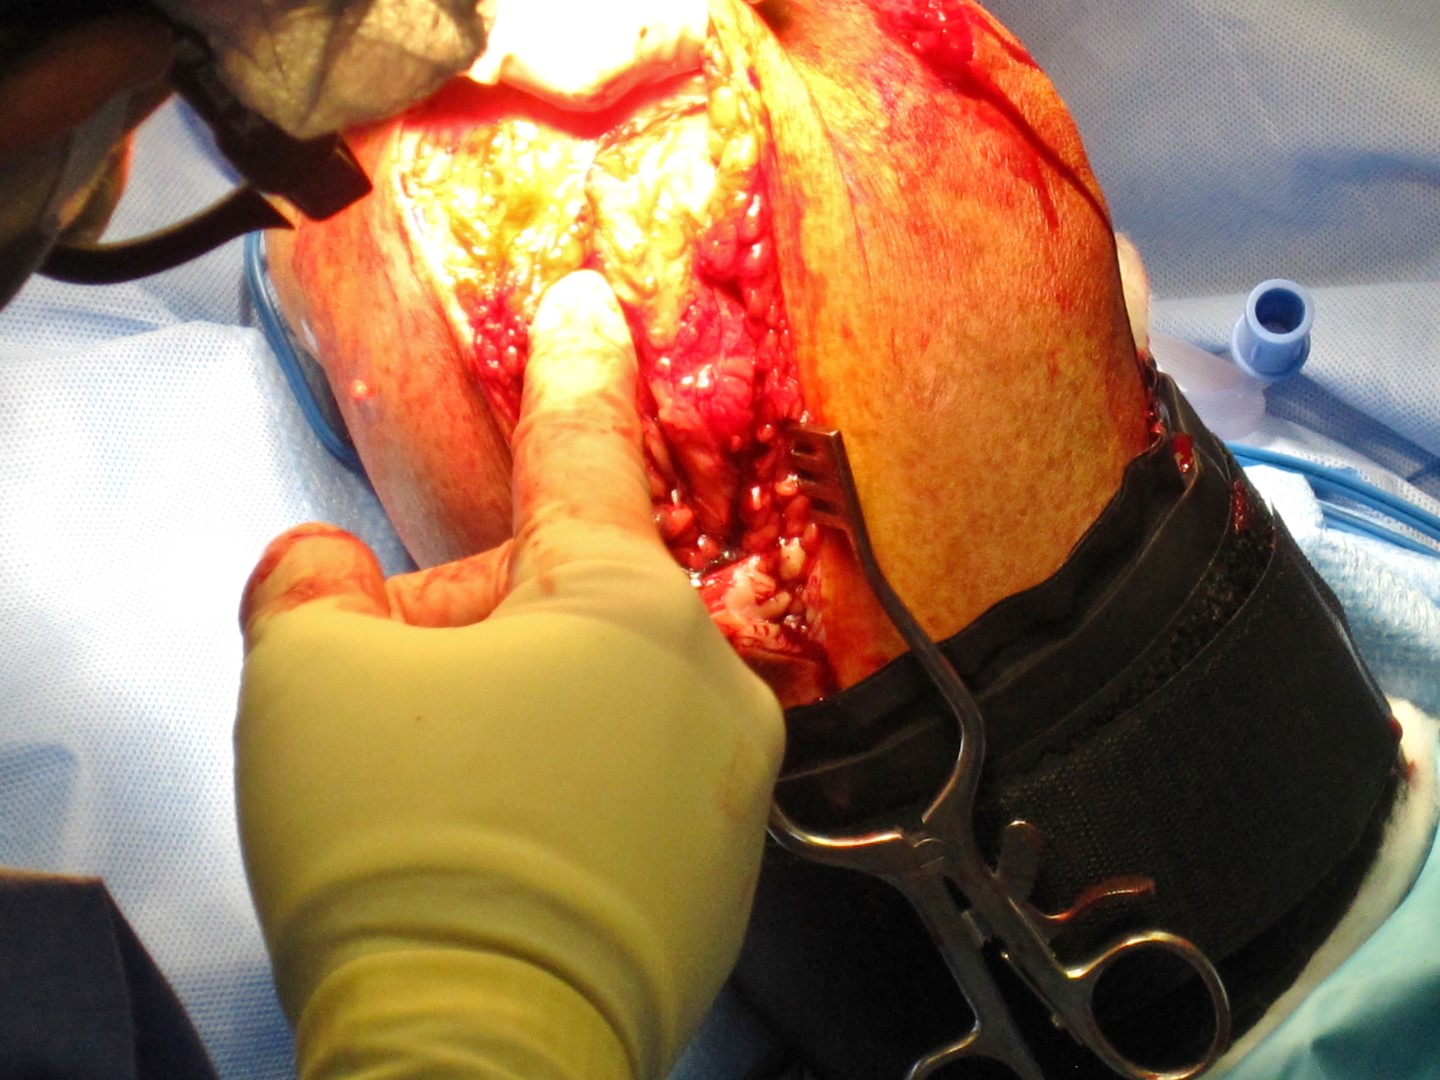

The surgeons notes say: “Left distal humerus fracture. Highly comminuted. Open fracture.”

This means the elbow end (distal) of my left upper arm bone (humerus) was badly shattered (highly comminuted) and bone was exposed thru the skin (open fracture).

After getting the bone healed, ligament damage was found that needed repaired. So, two “collateral ligament reconstruction” surgeries followed.